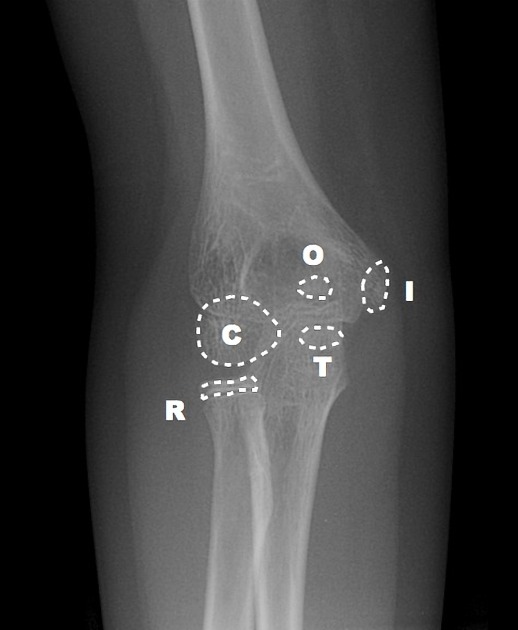

Elbow Interpretation Roadmap: CRITOE

More pragmatic and utilitarian than a prosaic mnemonic, CRITOE helps us to remember the order of ossification of the pediatric elbow.

Although children develop at different rates, the order of ossification is programmed into us.  Images courtesy of Radiopaedia.

Capitellum

By age one, the capitellum ossifies. On the AP view, imagine a little white oval balloon floating in the darkness between the radius and the humerus.

Radial Head

By age three, the capitellum gets another little balloon to join the party. The radial head is a bony little balloon that floats just above the floor.  If you see both little balloons floating on either ends of the space between the humerus and the radius – you know this child is about three years old.

Internal Epicondyle

By the age of five, the capitellum and radial head are no longer little floating balloons, but now taking on shapes that resemble what they will look like as an adult. By age five, you’ve grown out of balloons, and have moved on to Frisbees.  The internal epicondyle (meaning the medial epicondyle) starts to ossify by age five – a little bony Frisbee.

Trochlea

By age seven, another little Frisbee flies around. On the AP view, the trochlea is superimposed on the humerus – if you look at the distal medial humerus, you’ll see the trochlea like a little oval Frisbee taking shape (see combined film below).

Olecranon

By age nine, the olecranon of the ulna is ossifying.  In a nine year old, you’ll see a capitellum, radial head, internal epicondyle, trochlea, and olecranon.

External Epidondyle

By age 11, you start to ossify your external epicondyle (lateral epicondyle).

CRITOE gives us the order of ossification for the pediatric elbow – capitellum, radial head, internal epicondyle, trochlea, external epicondyle, and olecranon — typically occurring at year 1, 3, 5, 7, 9, and 11 – remember the order is the most important thing – all ossification centers should be accounted for.  Make sure one is not missing – or where one has been “created” traumatically.